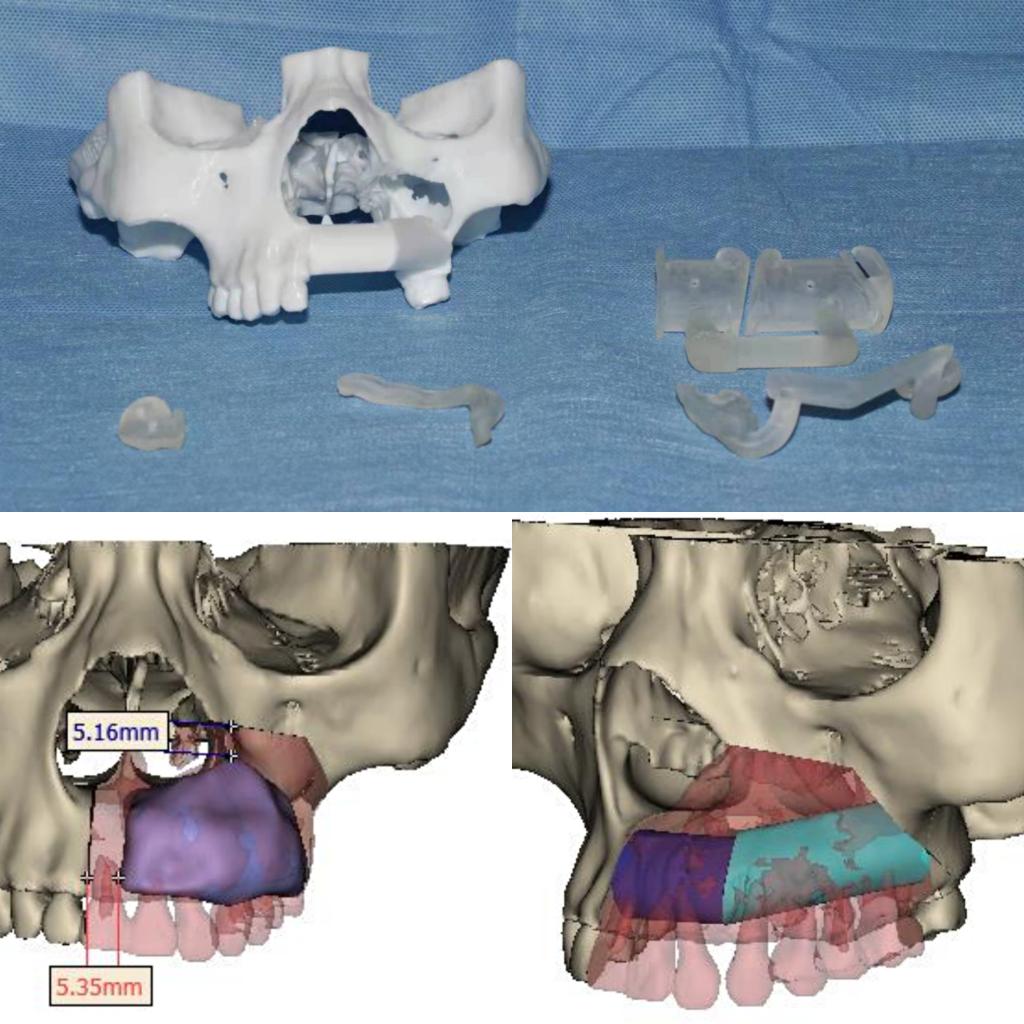

本次手术历时6个小时,吴亚东团队精确切除了患者左上颌骨肿瘤,利用数字化血管化腓骨瓣及个性化钛网重新恢复了这位年轻妈妈的面型及上颌骨缺损。术后在口腔颌面外科护理团队的精心护理下,患者病情恢复良好,现已治愈出院。面型基本对称,移植的腓骨瓣存活良好。半年后,这位年轻的妈妈就可以利用“新的上颌牙槽嵴”进行种植牙恢复咀嚼功能。

目前,口腔医院完成血管化骨瓣移植修复重建下颌骨、血管化肌皮瓣修复软组织缺损已超百例,技术成熟,各类骨肌皮瓣存活率极高。但上颌骨肿瘤因临近鼻腔、上颌窦、眼眶等重要复杂结构,缺损的形态不规则,切除后缺损的修复有极大难度。上颌骨切除术后会导致口鼻瘘、面型畸形、语言及进食障碍、甚至对病人及其家属造成巨大的心理障碍。口腔颌面外科致力于解决患者的病痛,利用计算机辅助设计 / 计算机辅助制造(computer assisted design/computer assisted manufacture,CAD/ CAM),精准切除肿瘤及修复上颌骨缺损。术前设计、术中准确控制以及术后可靠预测,手术可获得理想上颌骨重建效果。在满足患者外形需求的同时,还保障了相关功能,真正做到了个性化功能性修复重建。